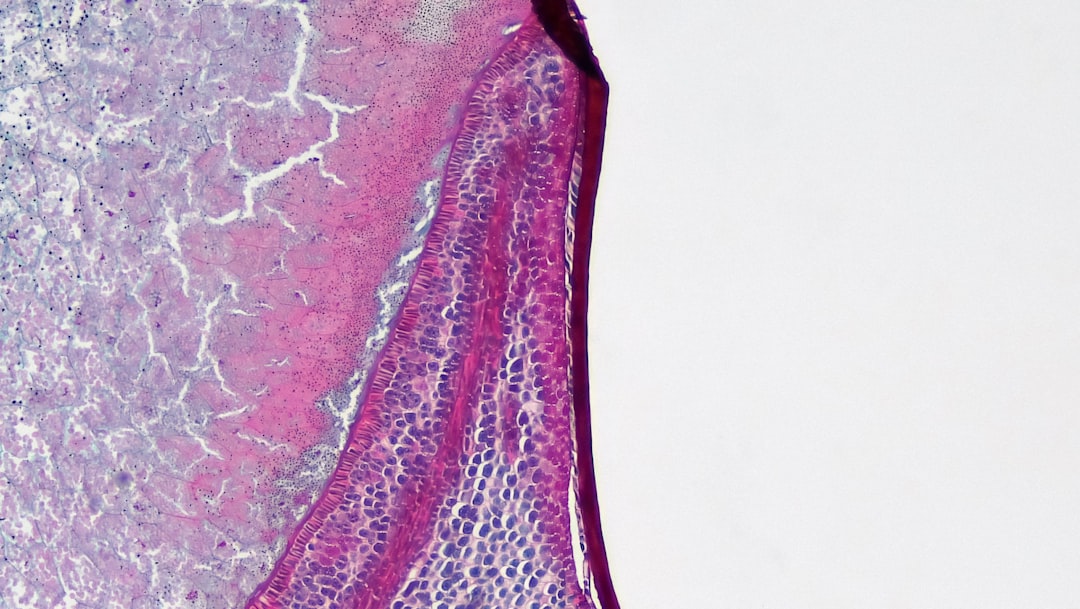

간경화는 간의 손상이나 염증이 지속적으로 발생하여 간세포가 죽고, 그 자리에 섬유조직이 자리를 차지하게 되는 질환입니다. 이러한 과정 중에 나타나는 것이 바로 간경화 초기증상입니다. 간은 우리 몸에서 매우 중요한 역할을 수행하기 때문에 이 초기증상을 잘 이해하고 관리하는 것이 중요합니다. 간경화 초기증상으로는 피로감, 체중 감량, 복부 팽창, 황달, 소양증 등의 다양한 증상이 있을 수 있습니다.